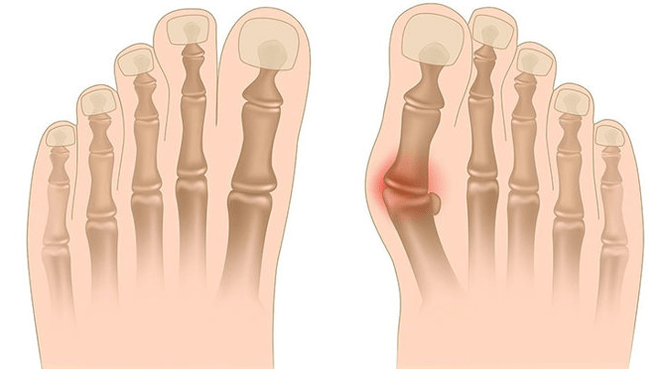

Valgus deformācija ir pēdas izliekums, kam raksturīga tās gareniskās arkas saplacināšana. Parasti pēdas iekšējā mala ir nolaista (“pilieni”), un papēdis izrādās.

Kad jūs paņemat kājas (ja skatāties uz tām no aizmugures), potītes līmenī veidojas X līdzīga deformācija: potītes ir saskarē, bet papēži atrodas 5-6 centimetru attālumā viens no otra.

- I - nav kaulu deformāciju, uz potītes iekšējās virsmas (aizmugurējā stilba kaula muskuļa stiprināšanas vietā) tiek noteiktas sāpes;

- II - viegls izliekums, papēdis ir nedaudz noraidīts;

- III - pēda ir piešķirta, un deformācija ir fiksēta (nav pareizi koriģēta);

- IV - izliekums tiek novērots ne tikai pēdā, bet arī potītes locītavā.

Nākamais slimības posms ir saistīts ar pēdas izliekuma rašanos: pacienti stāvošā stāvoklī nepaļaujas uz pēdas ārējo malu, bet gan ar visu savu teritoriju. Tiek novērotas nelielas izmaiņas gaitā.

Trešajā posmā tiek noteikts atkausētā kaula izvirzījums (manāmi zemāks par potīti uz potītes iekšējās virsmas), kā arī spēcīga papēža novirzīšana ārpusē (pacients stāv, pamatojoties uz papēža kaula iekšējo malu).

Pēdu uzlabotajai valgus deformācijai raksturo gan pašas pēdas, gan potītes locītavas izteikts izliekums. Pacienti sūdzas par sadedzināšanas sāpēm apakšstilba muskuļos, kā arī par būtisku gaitas pārkāpumu: ceļgali berzē viens pret otru, bet labās un kreisās pēdas atrodas zināmā attālumā.